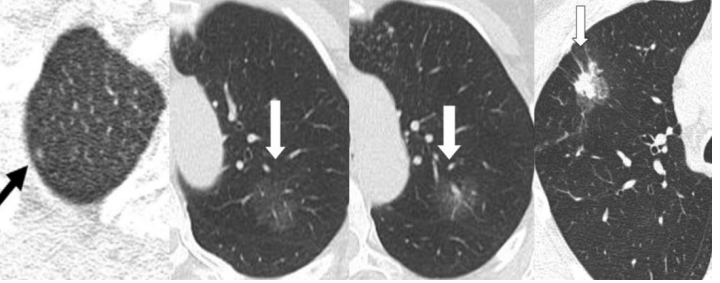

4、在定期复查中,发现病灶逐渐增大、颜色变实、实性成分增多(影像学表现为密度增加)要高度怀疑肺癌。

图五 恶性病灶影像学表现